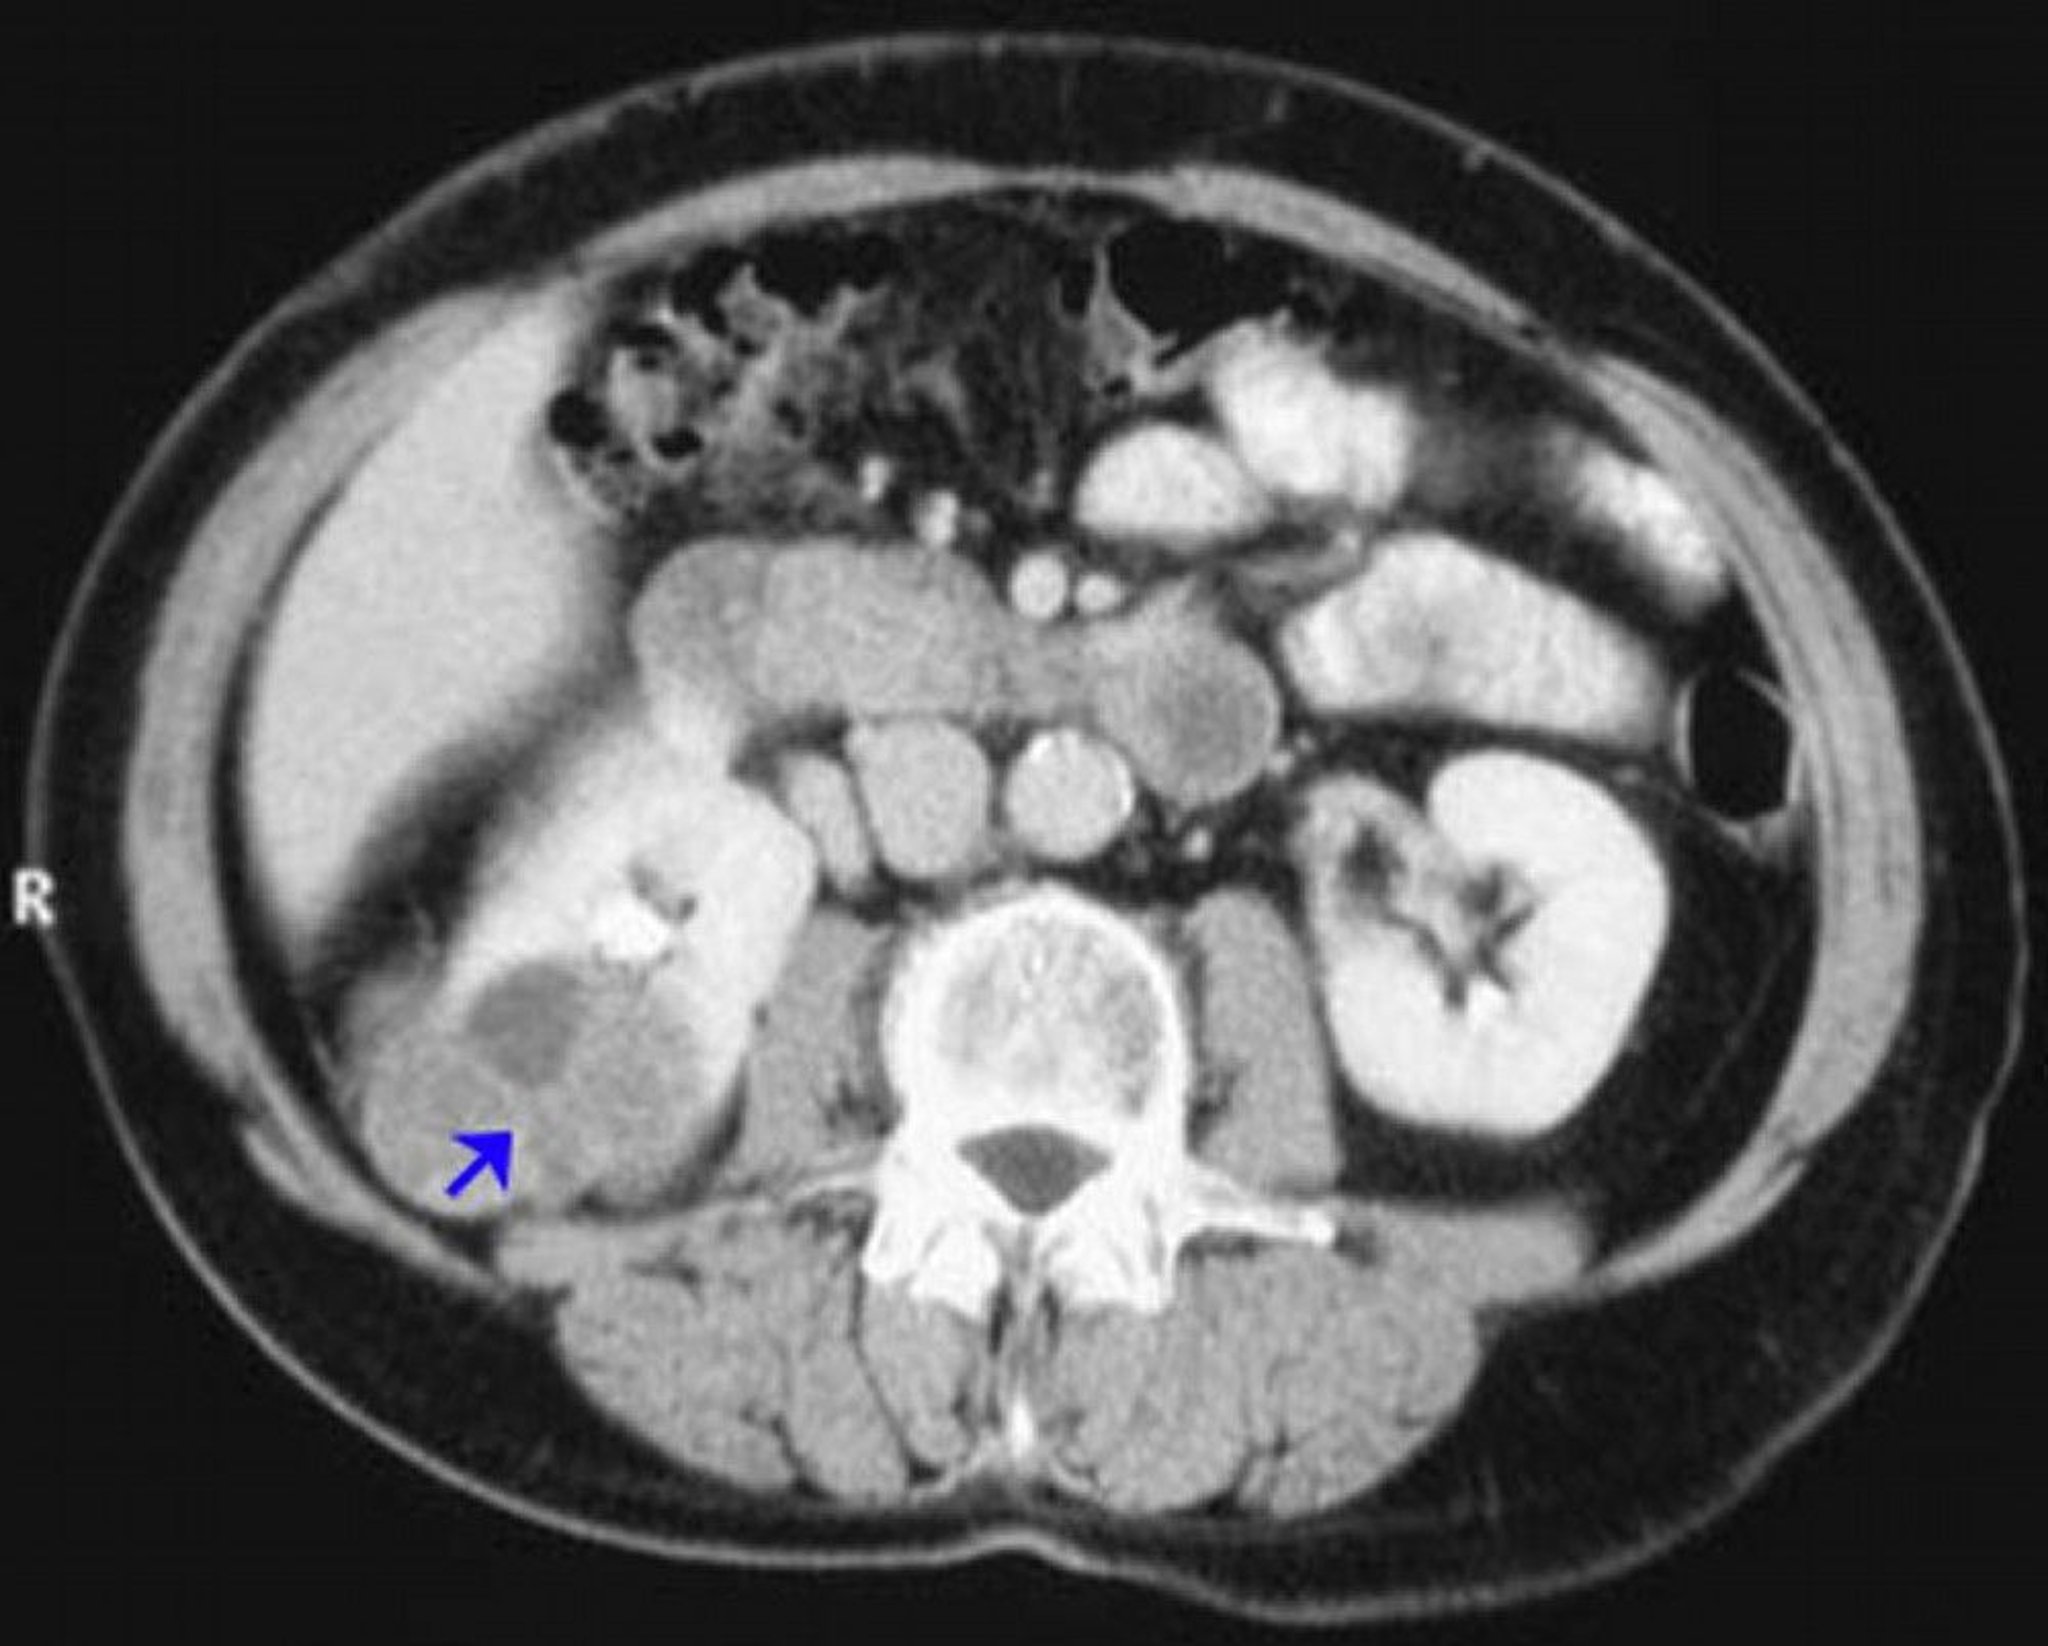

Carcinome à cellules rénales (TDM avec contraste)

Cette image montre un carcinome à cellules rénales du rein droit (flèche) montrant une tumeur qui prend peu le contraste.